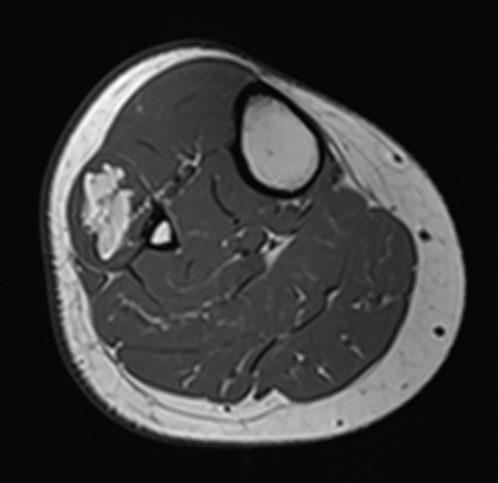

Liposarcoma anterior thigh

MRI

Deep to fascia / heterogenous